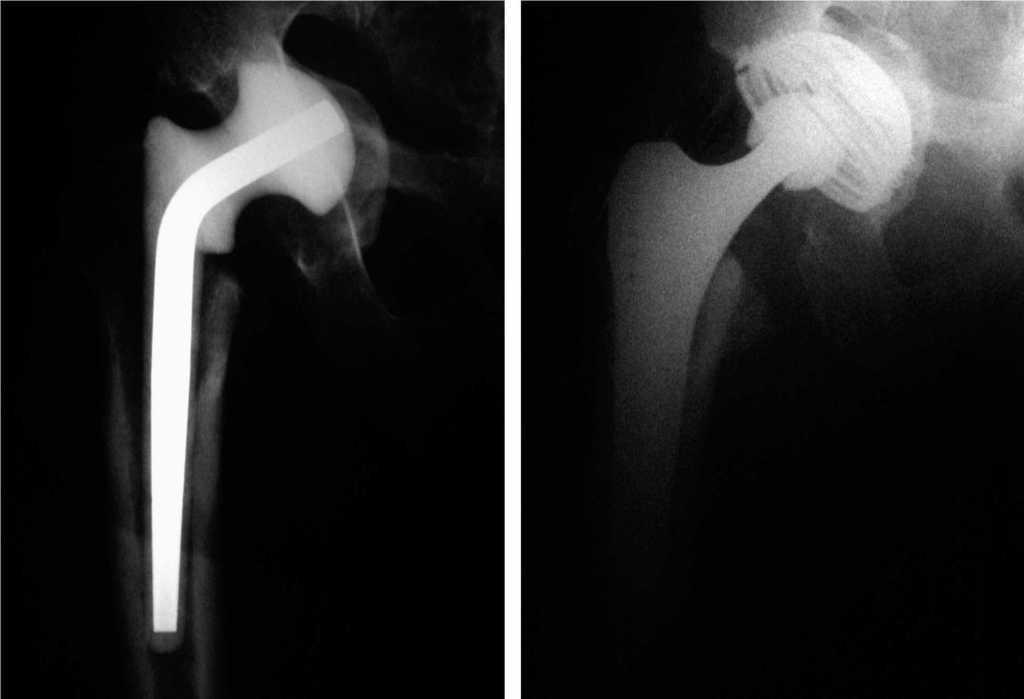

Tres semanas después, ante la mejoría clínica, se practicó una nueva intervención implantando un espaciador (fig. 2). A las ocho semanas del tratamiento antibiótico se retiró el espaciador y se colocó una prótesis total en su cadera afecta (fig. 2B). Fue dada de alta a los cuatro meses del inicio del proceso, siendo su evolución satisfactoria en los controles posteriores.

Figura 2. (A) Radiografía de control con el espaciador provisional. (B) Radiografía final, que muestra el resultado tras implantar una prótesis total.